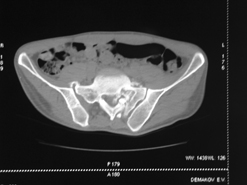

Диагноз : Сочетанная травма. ЗЧМТ. Перелом свода черепа. Ушиб головного мозга.Разрыв лонного и крестцово-подвздошного сочленений с нарушением целостности тазового кольца, с массивной забрюшинной гематомой и пропотеванием в брюшную полость. Перелом 10 ребра справа, осложненный гемопневмотораксом справа, правосторонней пневмонией на фоне ушиба правого легкого. Шок 3-4 ст. Больной поступил в отделение 07.03.2005г. в 16.00 в экстренном порядке через 30 минут после автодорожной травмы.Доставлен КСП. При поступлении состояние больного крайне тяжелое, явления травматического шока, А/Д-80/60 мм.рт. ст. ЧСС-120.В экстренном порядке поднят в операционную, интубирован, совместно с диагностическими мероприятиями лечение шока.При осмотре выявлены перелом 10 ребра справа, разрыв лонного и правого крестцово-подвздошного сочленений. Имеется линейный перелом теменной и височной костей слева с переходом на основание. Диагностическая лапароскопия 07.03.2005г. в 16.30-массивная забрюшинная гематома малого таза.Оставлена контрольная, дренажная трубка.Учитывая кровь в моче произведена цистография - данных за разрыв мочевого пузыря не найдено. Больной переведен в реанимационное отделение.За 08.03.2005г. из брюшной полости выделилось до 1500,0 мл, крови, часть крови реинфузирована. 08.03. в 06.30 наложен торокоцентез справа,удалено 100,0 мл. крови и 200,0 мл. воздуха .. Учитывая продолжающеееся кровотечение в брюшную полость из перелома костей таза, для исключения возможного разрыва внутренних органов 09.03.2005г. произведена Видеолапароскопия., на которой повреждения органов брюшной полости не выявлено.Одновременно произведен шов лонного сочленения проволокой и винтами, с одномоментным наложением стержневого аппарата на кости таза, с целью уменьшения кровотечения из разрывов тазовых сочленений, дренирование гематом. В последующем состояние больного оставалось тяжелым. 10.03.наложена нижняя трахеостома.Далее неоднократно производилась лечебно-диагностическая ФБС.С 10.03 выявлена правосторонняя плевропневмония. КТ головного мозга от 10.03-субарахноидальноекровоизлияние.Срединные структуры не смещены. КТ-контроль от 15.03-открытая моновентрикулярная гидроцефалия4 желудочка. Полисинусит. Постепенно состояние больного медленно прогрессировало к улучшению.С 24.03 переведен на самостоятельное дыхание, а 09.03 переведен в травматологическое отделение.Аппарат стержневой снят из-за перелома стержня (раскрутил больной самостоятельно).После госпитализации в наше отделение проведено дополнительное обследование Рентгекнография, КТ.Хотелось бы услышать Ваше мнение о дальнейшей тактике.-- С уважением, Leonid

Углядел билатеральное повреждение таза. Имеется вертикальная нестабильность со стороны перелома боковой массы крестца, ротационная с контрлатеральной стороны - чрезподвздошный разрыв кп сочленения. Разрыв лона, запирательные отверстия вроде целы.

DS. на сегодняшний день: Вертикальная двусторонняя нестабильная деформация таза, неправильно срастающийся перелом боковой массы крестца слева, срастающийся перелом крыла правой подвздошной кости, застарелый частичный разрыв правого кп сочленения, застарелый разрыв лонного сочленения.

План жизни - оперативное лечение. ЧКО таза (кольцевая опора), последовательная фиксация задних отделов с низведением перелома крестца, синтез лона пластинами, илиосакральное блокирование.